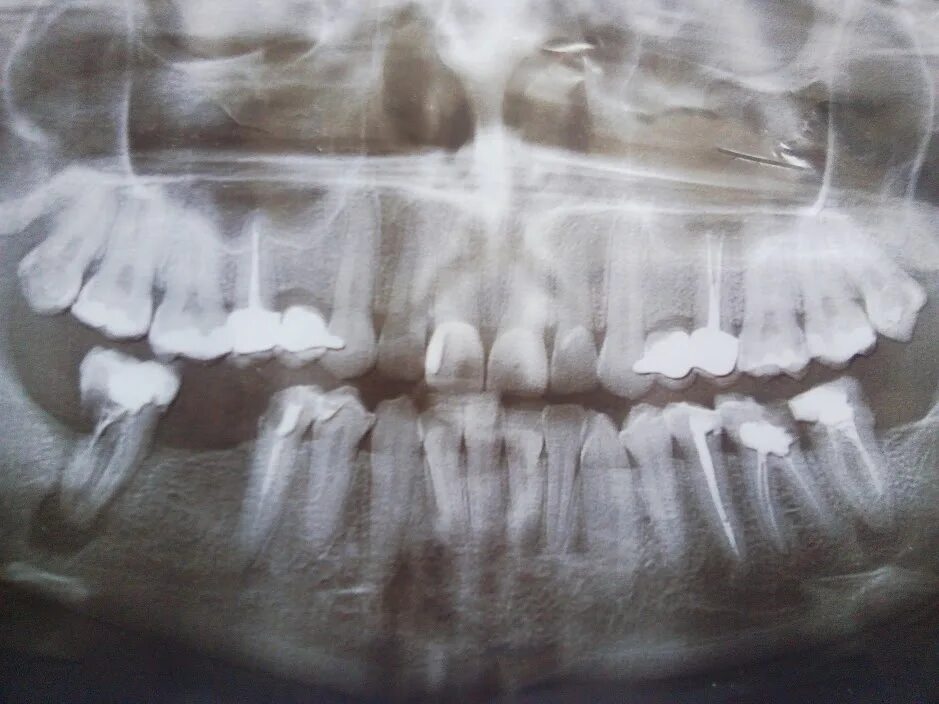

Киста зуба что это